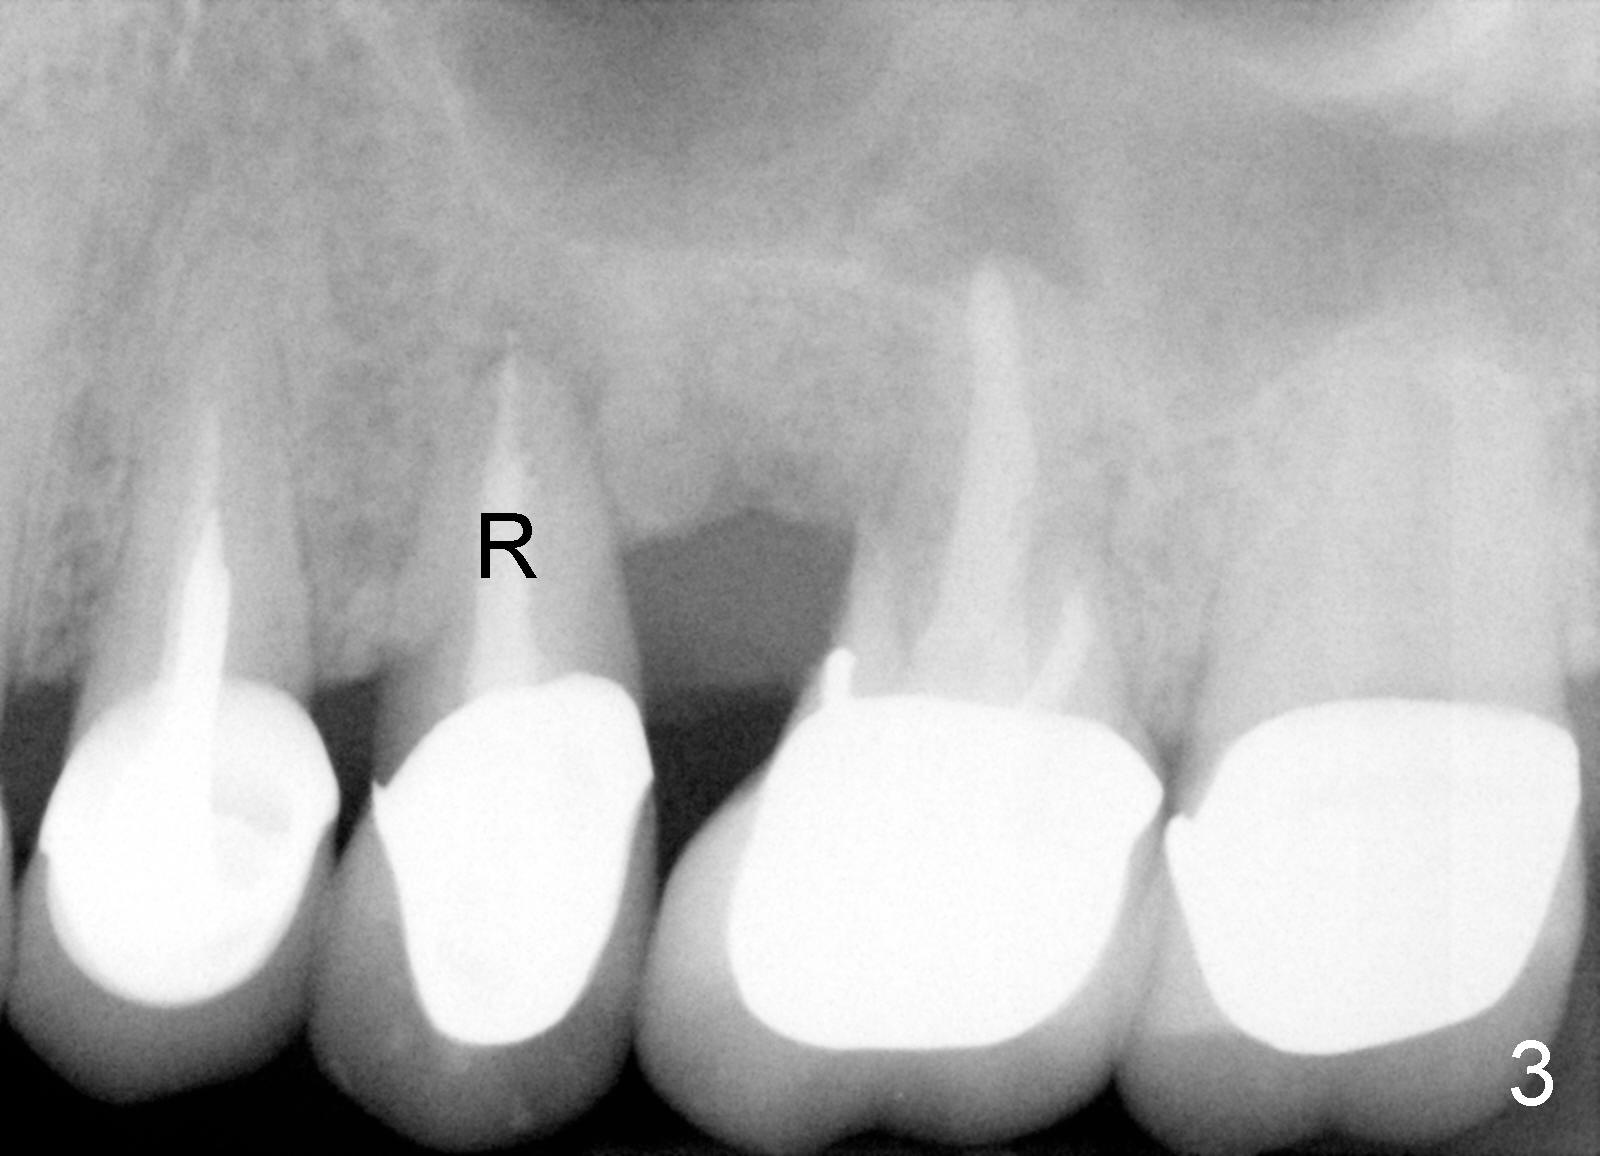

吴先生从小牙齿不好,挺能理解人,所以我们关系还能维持七八年。第一次他来时,我们诊所刚开张,没有多少病人,他左上第一磨牙近中根纵裂(图一:14**),花时间做根切(root amputation,切除近中根近中游离部分),其余两个根做根管治疗(图二)。不久以后他一直有轻微前臼齿区不适,好像第二前臼齿根管治疗充填不佳(图二<),根尖有阴影,不妨重做根管治疗(图三R),之后问题没有解决,根尖切除后,还是好好坏坏,那么再做一次根管治疗(图四R)。好不容易等到他认为疼痛来自于第一前臼齿:颊侧根充填不到位(图四箭头),鄂侧根好像有个牙桩(其实是银汞拴(Amalgam plug)),好像没有根充。这没有什么了不起:除去牙冠,牙桩,重做根管治疗,我们样样都能做。鄂侧根管很快搞通,但是颊侧根管根尖1-2 mm 阻塞,无可奈何。根充(30/.06 for L, 55 for P)后,插入两个三号Coltene Whaledent stainless steel posts以及做牙冠。每当他回来洗牙,汇报前臼齿区仍有不适,不知那颗牙齿有毛病时,对颊侧根管处理不当深感内疚,问题真得出于那里吗?